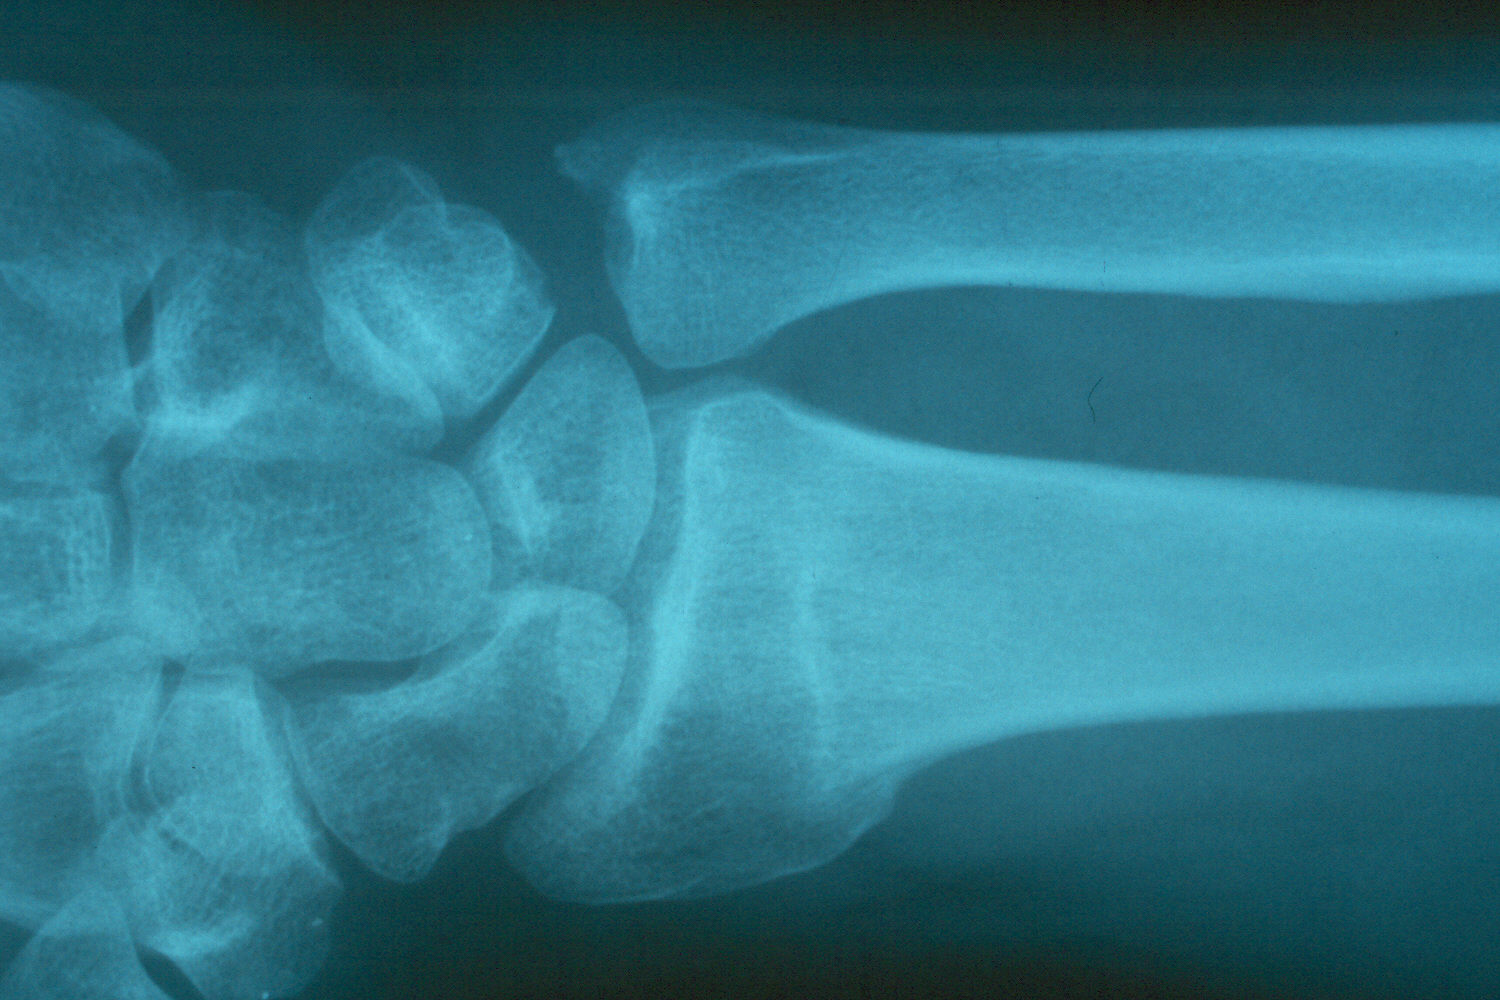

Preoperative radiographs demonstrate radial shortening and relative ulnar lengthening and ulnar carpal abutment.